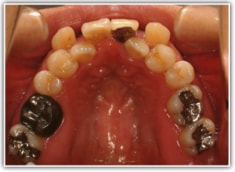

治療前

修復歯、補綴歯もあります。下顎8番が水平埋伏しています。